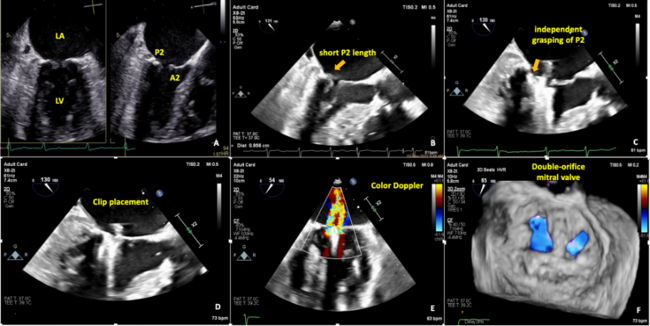

A 75-year-old woman with a history of heart failure was referred for dyspnea upon exertion due to severe mitral regurgitation (MR). Transesophageal echocardiography showed severe MR, which was attributed to the tethering of the posterior leaflet (scallop P2) due to the presence of mild posterior mitral annular calcification (MAC). The following mid-segment (A2) of anterior leaflet prolapse resulted in a small coaptation defect (Figure A). After Heart Team discussion, a MitraClip NTW (Abbott) procedure was planned. However, the presence of MAC, eccentric MR, and a short posterior leaflet suggested unfavorable outcomes.1

We made multiple attempts to simultaneously grasp both leaflets but were unsuccessful due to the short grasp length of the posterior leaflet (9 mm) (Figure B). Thus, we decided to grasp each leaflet individually and were initially able to grasp the more mobile anterior leaflet; however, capture of the posterior leaflet was still not feasible.

It was then decided to attempt to initially grasp the calcified posterior leaflet, despite the risk for its rupture due to stretching by the clip. The clip arms were opened at an angle of almost 160° and we were able to grasp the posterior leaflet (Figure C, Video 1); next, the anterior leaflet was successfully grasped (Figure D, Video 2). After clip placement, significant MR reduction with 2 distinct jets was detected (Figure E, Video 3), while 3-dimensional echocardiography showed a double-orifice mitral valve (Figure F, Video 4). After 3 months, the patient was asymptomatic with mild MR.